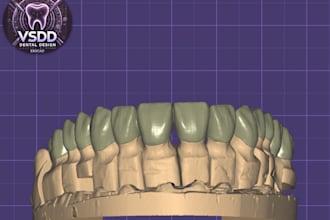

I will do dental prosthesis crown design using exocad, 3shape, inlab and cerec

From $20

Offers video consultations